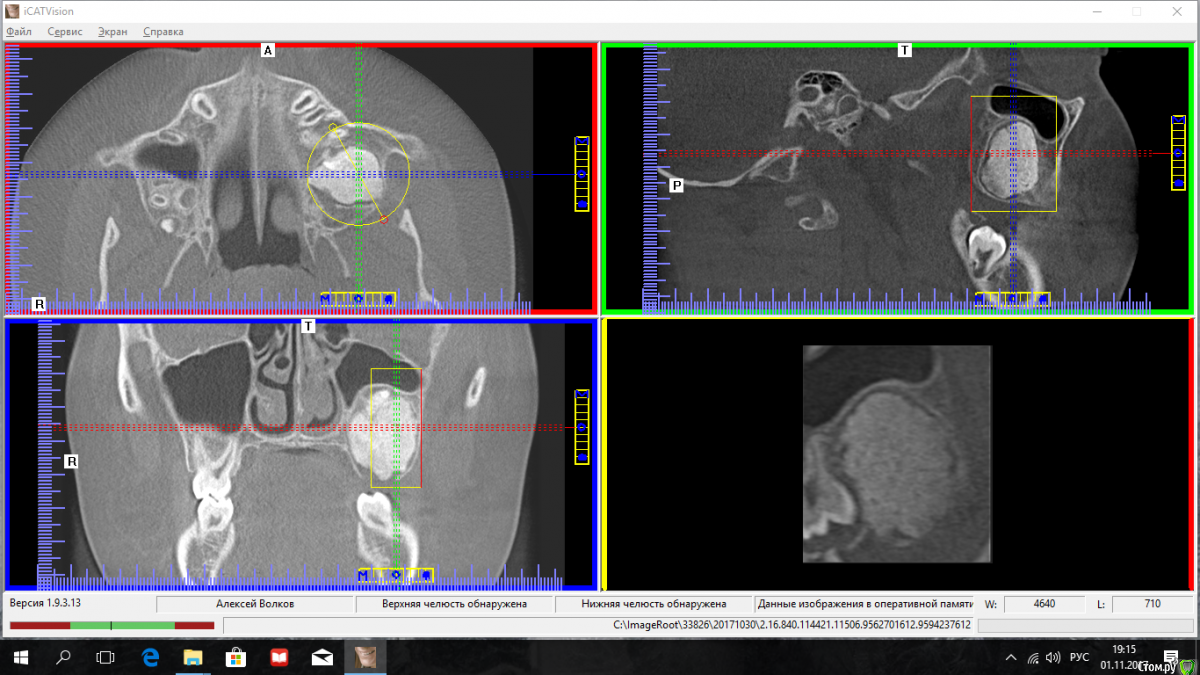

kriokov Опубликовано 1 ноября, 2017 Поделиться Опубликовано 1 ноября, 2017 мальчик 9 лет, одонтома в обл бугра, синус терпимо. Клиники нет. Но сам еще не смотрел, но думаю точно ничего не беспокоит. У кого есть опыт работы в "счастливом детстве" , подскажите-- сейчас или можно отсрочить, ? Ссылка на комментарий

kriokov Опубликовано 2 ноября, 2017 Автор Поделиться Опубликовано 2 ноября, 2017 заключение рентгенолога - одонтома , сложная, составная. Если кт крутить, то участки разной плотности, некоторые по плотности эмаль ну и структурно похоже на одонтому, На дисплазию по мне так совсем не тянет, -- граница, четче не бывает-раз, в верхнем полюсе образования видно просветление- это скорее всего часть капсулы-- два, разные по плотности участки в образовании -- три, отсутствие деформации - четыре, четко контурируемые кортикальные пластинки и в обл альвеолярного отростка и в обл дна синуса --пять. Может убрать? Дать шанс 6-ке? И нос посмотреть бы у "Лориков"лорики уже вгляделись, и вот , что поведали ---С обеих сторон определяется уменьшение носоглоточного пространства, за счет гипертрофии тканей области глоточной миндалины, также небных миндалин, с неровными, фестончатыми контурами за счёт дольчатого строения-аденоид, который с обеих сторон перекрывает средний носовой ход.При исследовании визуализируются височные кости, структуры внутреннего уха справа и слева дифференцируются, сосцевидные отростки височных костей пневматического типа строения. Барабанная полость справа и слева, наружные и внутренние слуховые проходы свободны.Конечно, шестой должен жить должен, согласен. 1 Ссылка на комментарий